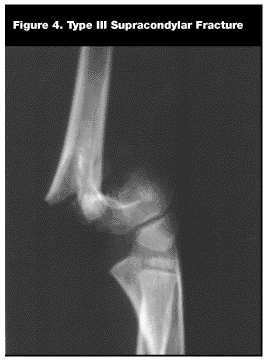

Elbow. Supracondylar. Supracondylar fractures are the most common elbow fracture in children.1,3,8 Most fractures occur in children between 3 and 10 years of age. A fall on an outstretched arm with hyperextension of the elbow is the most common mechanism of injury. Three types of supracondylar fractures commonly are described.8 Type I is a nondisplaced fracture. Type II is a displaced and angulated fracture but with the posterior cortex intact. Type III is a completely displaced fracture with no cortical contact. (See Figure 4.) Most type III fractures have the distal fragment displaced posteriorly.

On physical examination, pain with flexion of the elbow often is noted and tenderness over the distal humerus usually is present. The swelling varies depending on the type of fracture and associated underlying neurovascular injury. The assessment of the distal neurovascular status is especially important in this type of fracture. Increasing pain and/or paresthesias are worrisome signs and may signal a compartment syndrome.4,5,8 AP and true lateral radiographs should be obtained after splinting. Type I fractures may be subtle, and attention should be paid to alignment of the anterior humeral line and posterior fat pad sign.